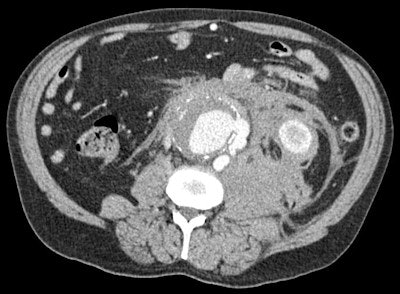

A middle-aged patient with abdominal pain considered on clinical grounds to be due to diverticulitis. Contrast-enhanced CT reveals active retroperitoneal haemorrhage from an actively leaking abdominal aortic aneurysm. Radiology (CT in this case) completely alters the diagnostic thinking and the therapeutic strategy, thereby having an impact on the outcome of the patient, who survived aortic surgery. Image courtesy of Dr. Adrian Dixon.

A middle-aged patient with abdominal pain considered on clinical grounds to be due to diverticulitis. Contrast-enhanced CT reveals active retroperitoneal haemorrhage from an actively leaking abdominal aortic aneurysm. Radiology (CT in this case) completely alters the diagnostic thinking and the therapeutic strategy, thereby having an impact on the outcome of the patient, who survived aortic surgery. Image courtesy of Dr. Adrian Dixon.Another means of enhancing the profile of radiology is through radiologists publishing more radiological outcome studies to help prove to clinical colleagues that new methods are worth applying.